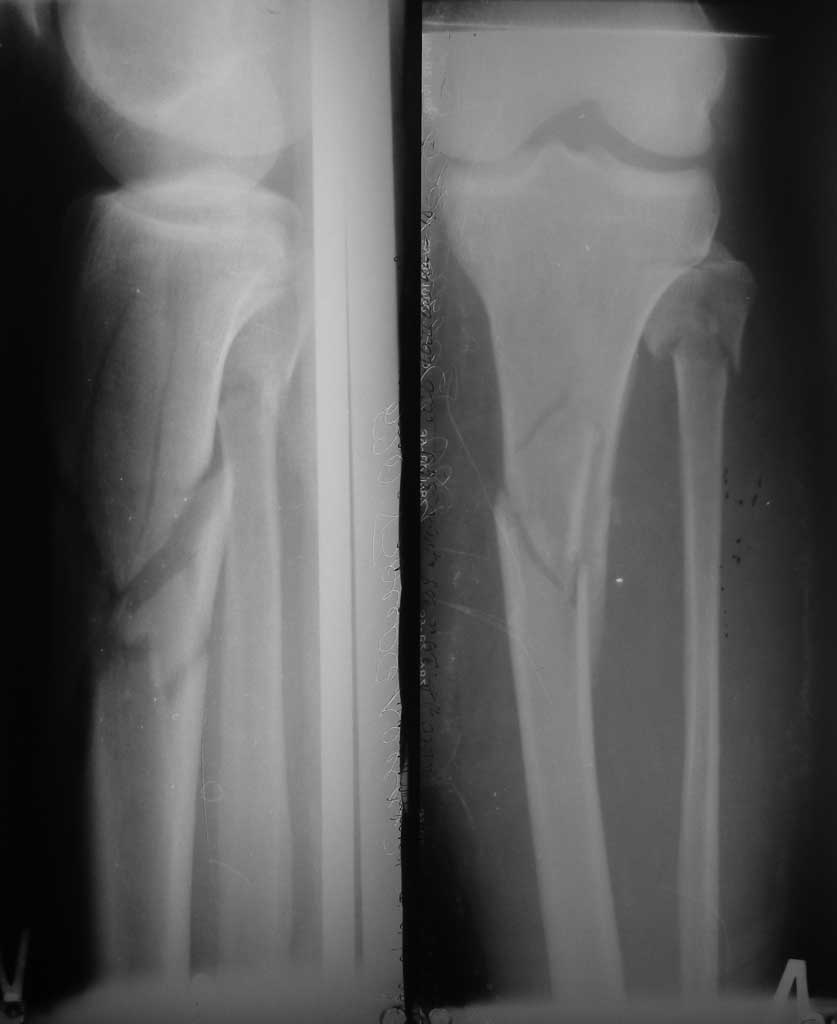

Похожий случай, вчера прооперировали. Непрямая репозиция, малоинвазивный остеосинтез без обнажения зоны перелома.

Уважаемый Марк!

Не так важно, какую пластину Вы выберете. Важно то, как Вы её поставите. Мы в подобных случаях используем пластину в качестве мостовидной и имплантируем её малоинвазивно, контролируя положение отломков, пластины и винтов ЭОПом. При этом не стремимся к идеальной репозиции, а восстанавливаем только ось, длину и устраняем ротационные смещения. Если после этого есть сомнения в медиальной стабильности, Накладываем медиально моноплоскостной наружный фиксатор на непродолжительное время. Он намного предпочтительнее второй пластины в биологическом смысле. Традиционный остеосинтез со вскрытием зоны перелома также возможен.